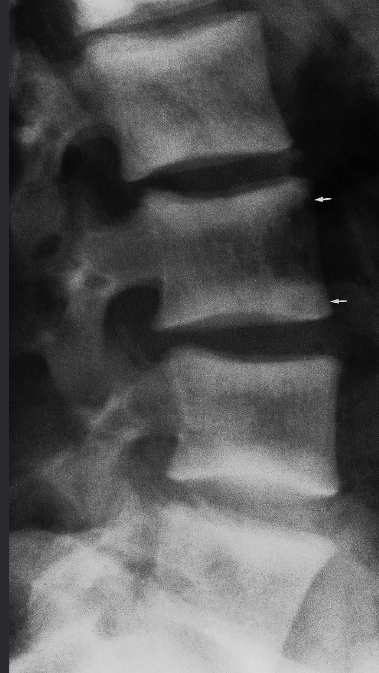

Modality X-ray lumbar spine (lateral view)

Findings Anterior displacement of L4 on L5 is visible. In addition, there is degenerative disk disease with narrowing of the L4–L5 disk space.

Diagnosis Disc Space Narrowing e.g. degenerative disc disease; Associated with endplate sclerosis and osteophytes